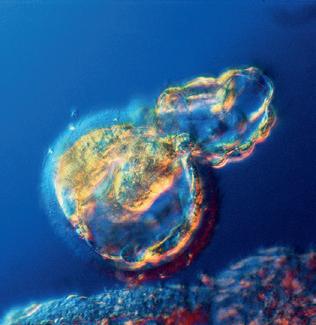

< Blastocysten på väg att landa i livmodern, men först måste den göra sig fri från det omgivande äggskalet.

Under kläckningen tumlar blastocysten runt inne i livmodern. Av och till stöter den emot den mjuka livmoderslemhinnan. Äggskalet brister och den ömtåliga cellmassan kommer ut.

(nästa uppslag) Efter kläckningen vidgar sig embryot snabbt och skulle inte längre få plats i skalet, som inte längre behövs. Sakta sjunker den fredliga inkräktaren in i livmoderns slemhinna.

Ägget tumlar runt.

Ägget kläcks.

När blastocysten väl tagit sig igenom äggledaren och kommit ut i livmodern finns det gott om utrymme. Livmodern är väl förberedd. Efter ägglossningen har livmoderslemhinnan haft drygt sex dagar på sig för att bli riktigt fint utvecklad, det vill säga just den tid det tar för ägget att komma ut ur äggblåsan, befruktas i äggledaren, färdas mot livmodern och landa på rätt ställe. Embryot ”väljer” noga den plats i livmodern där det ska slå sig ner. Man tror att det skickar ut kemiska signaler till sin omgivning och att omgivningen svarar på invitationen genom att erbjuda en bra miljö för utveckling och tillväxt. Strax före landningen i slemhinnan drar sig blastocysten samman och sväller upp igen minst tre fyra gånger. Embryot och moderkakan gör sig av med sitt omgivande skal – ett slags kläckning sker. Om embryot är friskt och utvecklingsbart lyckas kläckningen och det genomskinliga, tomma skalet seglar iväg och löses upp.

Skalets utsida har varit relativt jämn och hård, men ytan hos den nykläckta cellmassan är mer böljande i sin form och dessutom mycket klibbigare – det är som om hela embryot har doppats i sockerlag. Sockermolekylernas utskott sträcker sig mot livmoderslemhinnans yta, som i sin tur har likartade sockermolekyler där utskotten passar in.

Den allra första kontakten mellan embryot och livmoderns slemhinna är en kritisk process där många faktorer måste samverka på bästa sätt för att allt ska fungera. Det är embryocellerna och inte moderkakscellerna som tar initiativet till vidhäftningen i livmoderns slemhinna, den så kallade implantationen. Oftast fäster embryot i livmoderns övre del.